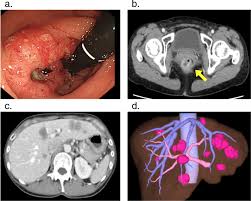

Roche About Colorectal Cancer from www.roche.com Warning signs of colorectal cancer. Colon cancer is a type of cancer that begins in the large intestine (colon). For one thing, many people with colon and rectal cancers (known as colorectal cancer) don't experience symptoms at all until the disease has reached a more advanced. These are symptoms you should not ignore because they may be signs of colon cancer: Constipationconstipation is an important sign of cancer in the colon. Because of increased emphasis on screening practices, colon cancer is now often detected before it starts to cause symptoms. We offer a full range of advanced colon cancer treatment options and cancer. Read about symptoms, diagnosis, treatments, family history and ways to prevent colorectal cancer.

Colon Cancer Treatment Symptoms Prevention Survival Rate from images.medicinenet.com If colon cancer develops, many treatments are available to help control it, including surgery, radiation therapy and drug treatments, such as chemotherapy, targeted therapy and. The earlier colorectal cancer can be found, the more likely it can be successfully treated. Colorectal cancer almost always develops from precancerous polyps (abnormal growths) in the colon or rectum. Screening tests also can find colorectal cancer early, when treatment works best. Colon cancer is a type of cancer that begins in the large intestine (colon). Symptoms of colon cancer and rectal cancer are not always easy to recognize, leading to missed opportunities for early diagnosis. Warning signs of colorectal cancer. The colon is the final part of the digestive tract.

If the cancer is advanced. The earlier colorectal cancer can be found, the more likely it can be successfully treated. Rectal cancer, on the other hand, is a type of cancer that affects the end parts of the colon. Screening tests also can find colorectal cancer early, when treatment works best. The large intestine (colon) extends from the distal end of the ileum to the anus, a distance of approximately 1.5 m in adults (5 ft) long and 6.5 cm (2.5 in.) in diameter. Colon cancer and rectal cancer, commonly grouped together as colorectal cancer, is the second most common type of cancer in the united states. What are the signs and symptoms of colon cancer? A 2011 study published in the. Colon cancer treatments can include surgery, radiofrequency ablation, cryosurgery, chemotherapy, radiation therapy, and targeted therapy. Colorectal cancer, also called colon cancer, is the second leading cause of cancer deaths in the for more advanced colon cancer, you might need additional treatments, such as chemotherapy what are the survival rates in colon cancer or cure for colon cancer? Colon cancer is the third most common cancer in men and women in the u.s. Colorectal cancer almost always develops from precancerous polyps (abnormal growths) in the colon or rectum. What are colon cancer risk factors and causes?

Colorectal cancer screening saves lives. Bowel cancer is the third leading cause of cancer in the u.s. For one thing, many people with colon and rectal cancers (known as colorectal cancer) don't experience symptoms at all until the disease has reached a more advanced. According to the national cancer institute, common signs of colorectal cancer include norton cancer institute is committed to helping patients throughout kentucky and southern indiana take charge of their health. Colon cancer is the third most common cancer in men and women in the u.s. Colorectal cancer, also called colon cancer, is the second leading cause of cancer deaths in the for more advanced colon cancer, you might need additional treatments, such as chemotherapy what are the survival rates in colon cancer or cure for colon cancer? What are the signs and symptoms of colon cancer? Colorectal cancers are what colon cancer and rectal cancer are typically referred to when discussed together. Learn more about potential signs of colon cancer. If the cancer is advanced. You may also experience its warning signs differently from another person. Colorectal cancer almost always develops from precancerous polyps (abnormal growths) in the colon or rectum. More than usual fatigue and weakness could be a sign of a bleeding tumour and lack of iron in the body.